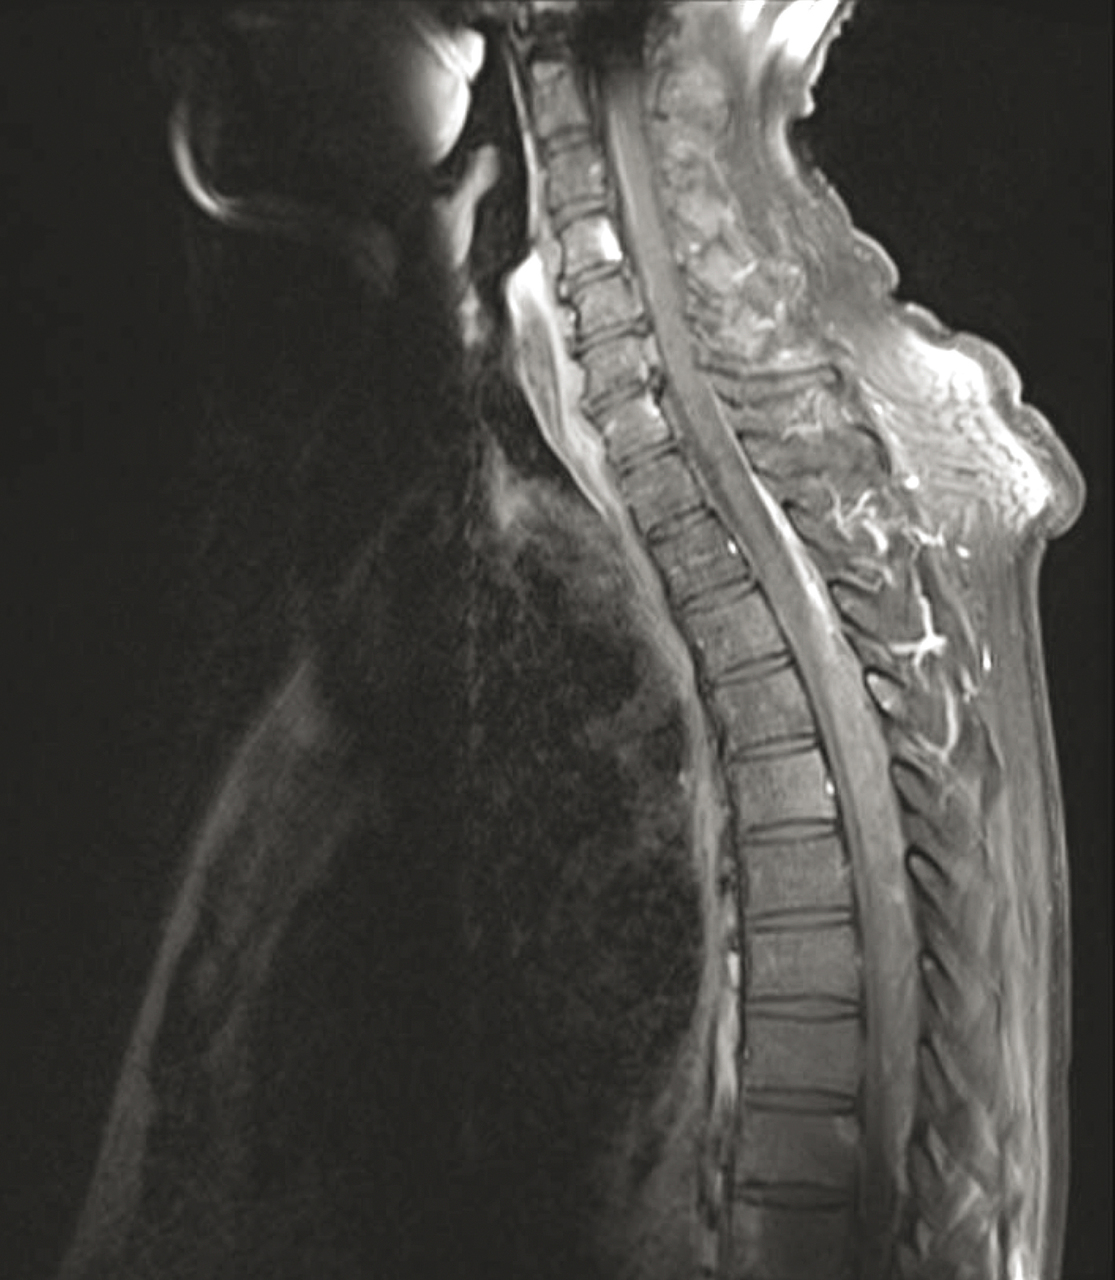

Quel est votre diagnostic ? Épidurite lymphomateuse Il s'agit d'une épidurite lymphomateuse.Pour en savoir plus : - Macro M. Myélome multiple des os. Rev Prat 2015;65(8):e69-77. - Rajzbaum G et al. Dossier Lomboradiculalgie des membres inférieurs. Rev Prat 2016;66(4):377-96. Hématome péridural Mal de Pott Neurosarcoïdose Syringomyélie OK Valider mes réponses